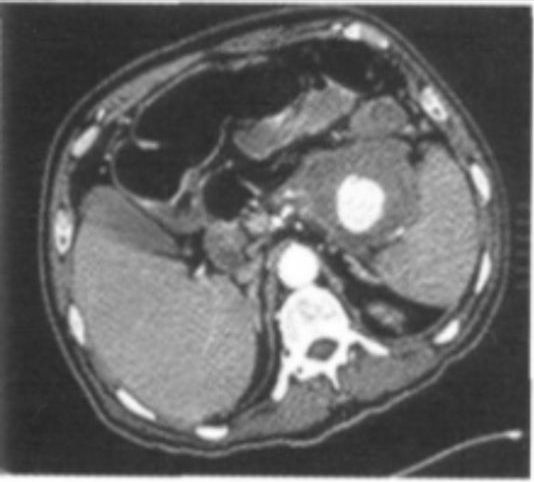

查体:心率90次/min,血压100/70mmHg,神志清楚,贫血貌,腹部平软,全腹部无压痛及反跳痛,肝脾肋下未触及。入院后血常规血红蛋白(HGB)84g/L;入院12h后再次发生新鲜血便,共5次,共500ml。心率升至124次/min,血压110/75mmHg。图1 腹部增强 CT。

诊断疾病胰腺假囊肿结肠瘘便血下消化道出血1、入院后保守治疗:积极抢救,给予输红细胞悬液、止血、扩容等治疗,改善一般状态。2、手术治疗:急诊于手术室中行肠镜检查,于横结肠近结肠脾曲见大量血凝块堵塞肠腔,内镜无法通过,未见明确出血位置。后急诊行DSA检查,未见明确出血病灶。急诊行腹部增强CT(图1),结果回报:考虑慢性胰腺炎并胰体尾部假囊肿,该病变侵蚀脾动脉并脾动脉瘘,与结肠脾曲关系密切,考虑存在该病变与结肠脾曲瘘。遂行手术止血。术中见胰体尾部假囊肿,该病变侵蚀脾动脉并脾动脉瘘,且与结肠脾曲瘘,导致下消化道出血,术中行脾切除、胰体尾切除、结肠脾曲切除肠吻合术。术后病理回报示:〔腹腔〕(胰腺体尾部)慢性胰腺炎,伴假性囊肿;(结肠脾曲)慢性溃疡,多灶性,局部穿孔,穿孔处与胰腺假性囊肿相通。3、术后行呼吸机辅助治疗,20d后痊愈出院。